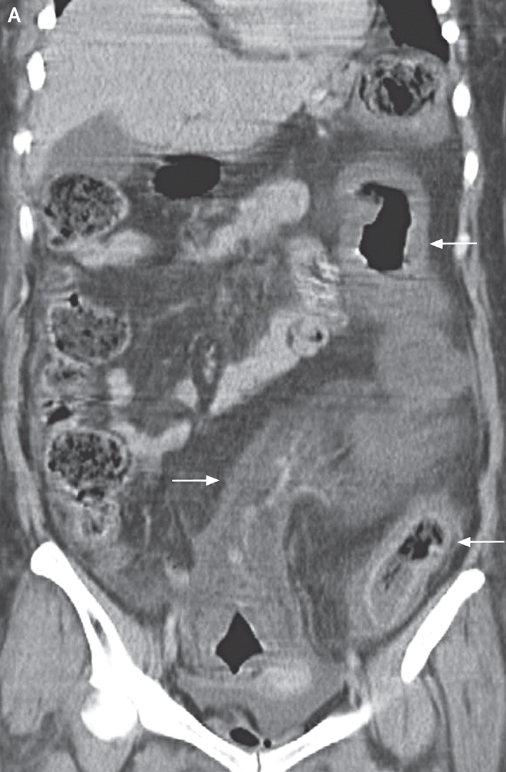

考虑抗生素相关性伪膜性肠炎一例